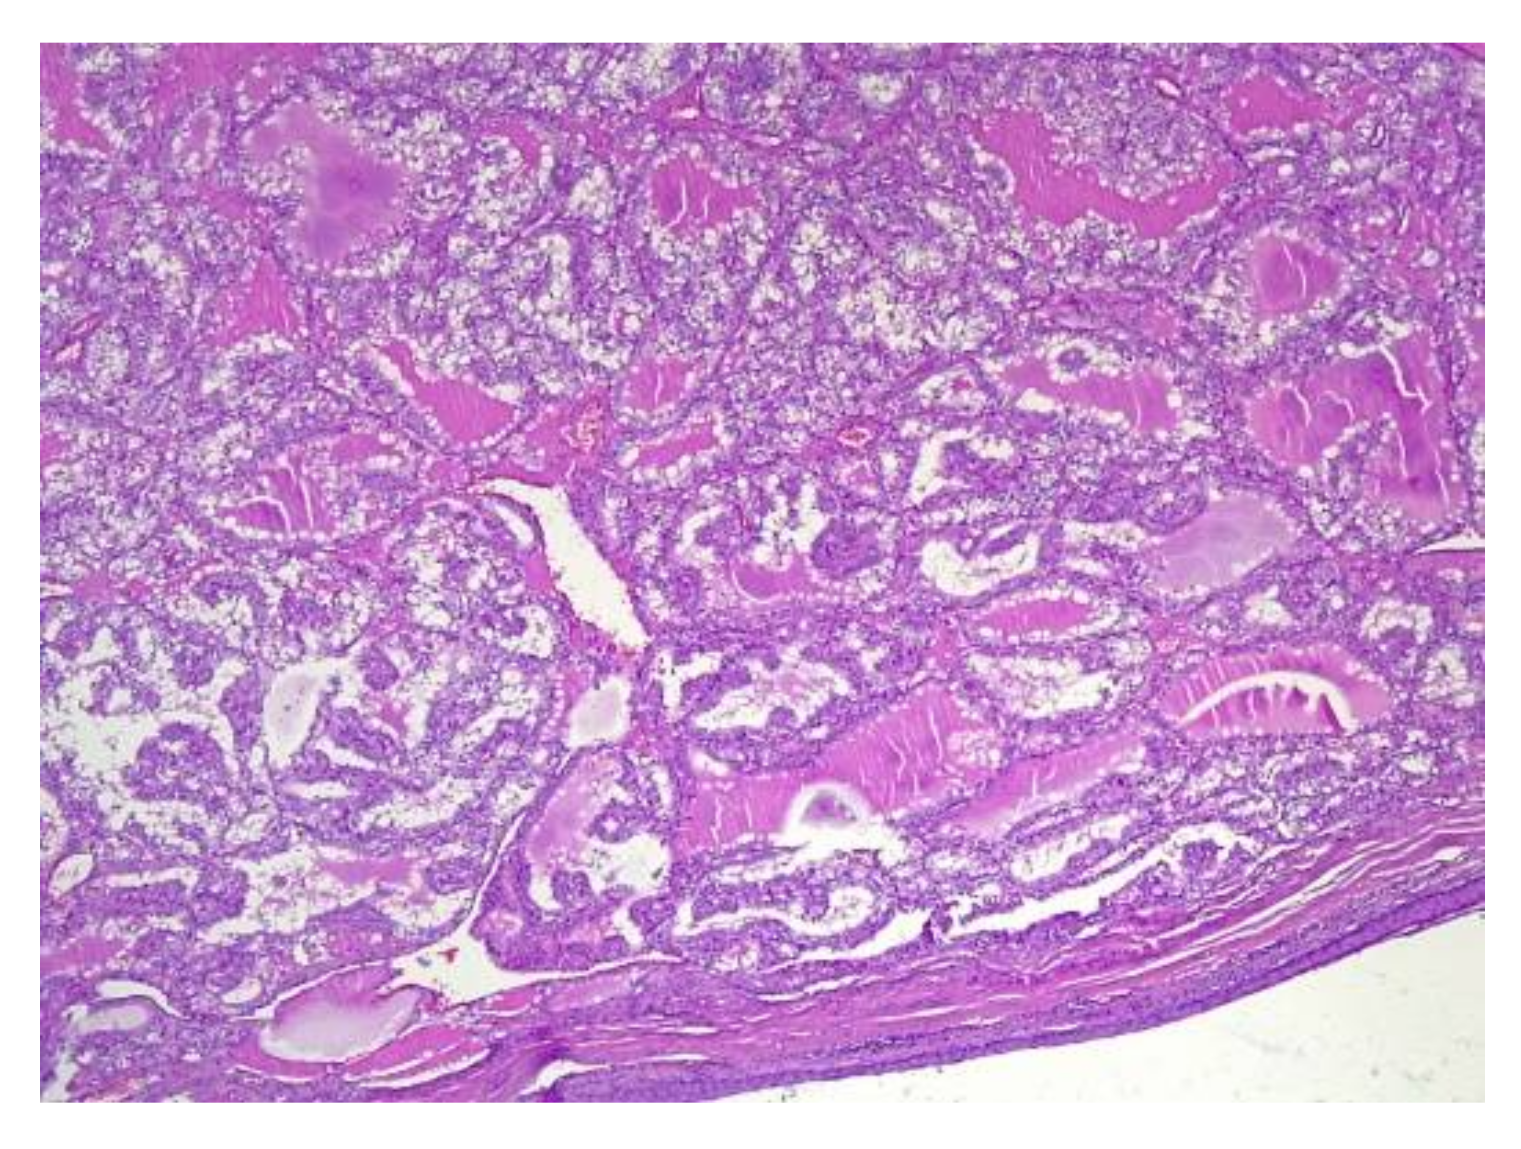

4.2. Histopathology Features